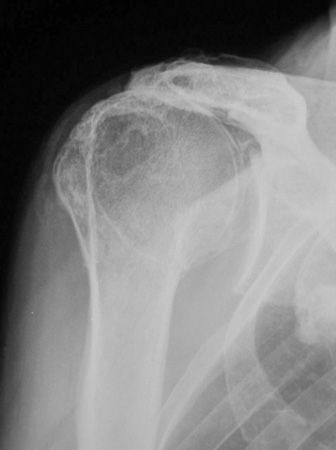

Technique Comment implanter une prothèse d'épaule inversée ? , Philippe Valenti Institut de la main - Clinique Jouvenet, Paris, France , D. Katz Clinique du Ter, 56270 Ploemeur - N°148 - Novembre 2005 ● 19 min de lecture

Mise au point La prothèse inversée d'épaule dans les ruptures massives et irréparables de la coiffe des rotateurs , M. Juvenspan Hôpital Saint Antoine – 75012 Paris , Geoffroy Nourissat Hôpital Saint-Antoine, 75012 Paris, France 🖂 gnourissat@wanadoo.fr , Levon Doursounian Hôpital Saint-Antoine, 75012 Paris, France 🖂 levon.doursounian@sat.aphp.fr N°148 - Novembre 2005 ● 15 min de lecture